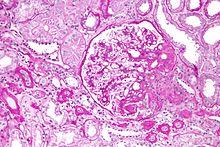

Kidney biopsy showing focal segmental glomerulosclerosis, one of the causes of nephrotic syndrome commonly seen in children.

Hypoalbuminemia can also present as part of the nephrotic syndrome, in which significant quantities of protein are lost in the urine due to kidney damage. Under normal conditions, less than 30 milligrams per day of albumin are lost via the glomerulus.[3] In nephrotic syndrome, protein loss can be as great as 3.5 grams over 24 hours, much of which is albumin, itself leading to hypoalbuminemia.[3] In children, nephrotic syndrome is commonly a primary disease process that is largely idiopathic, although more genetic causes are being identified with the cost and accessibility of whole exome sequencing. After renal biopsy, these syndromes are commonly diagnosed as minimal change disease, membranoproliferative glomerulonephritis, or focal segmental glomerulosclerosis.[9] In adults, on the other hand, nephrotic syndrome is commonly a secondary disease process due to a variety of inciting factors. These inciting factors can be diverse, including toxins, drugs, heavy metals, autoantibodies, post-infectious antibody complexes, or immune complexes formed after malignancies like multiple myeloma.[3]